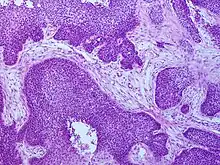

Appearance of basaloid pattern of squamous cell cancer under the microscope

Basaloid pattern of squamous cell cancer

Cancers of the oropharynx primarily arise in lingual and palatine tonsil lymphoid tissue that is lined by respiratory squamous mucosal epithelium, which may be invaginated within the lymphoid tissue. Therefore, the tumour first arises in hidden crypts. OPC is graded on the basis of the degree of squamous and keratin differentiation into well, moderate or poorly (high) differentiated grades. Other pathological features include the presence of finger-like invasion, perineural invasion, depth of invasion and distance of the tumour from resection margins. Phenotypic variants include basaloid squamous carcinoma, a high grade form (see Chung Fig. 35-3(C)[28] and illustration here). They are most commonly non-keratinising. HPV+OPC also differs from HPV-OPC in being focal rather than multifocal and not being associated with pre-malignant dysplasia. HPV+OPC patients are therefore at less risk of developing other malignancies in the head and neck region, unlike other head and neck primary tumours that may have associated second neoplasms, that may occur at the same time (synchronous) or a distant time (metachronous), both within the head and neck region or more distantly. This suggests that the oncogenic alterations produced by the virus are spatially limited rather than related to a field defect.[29][28][30]